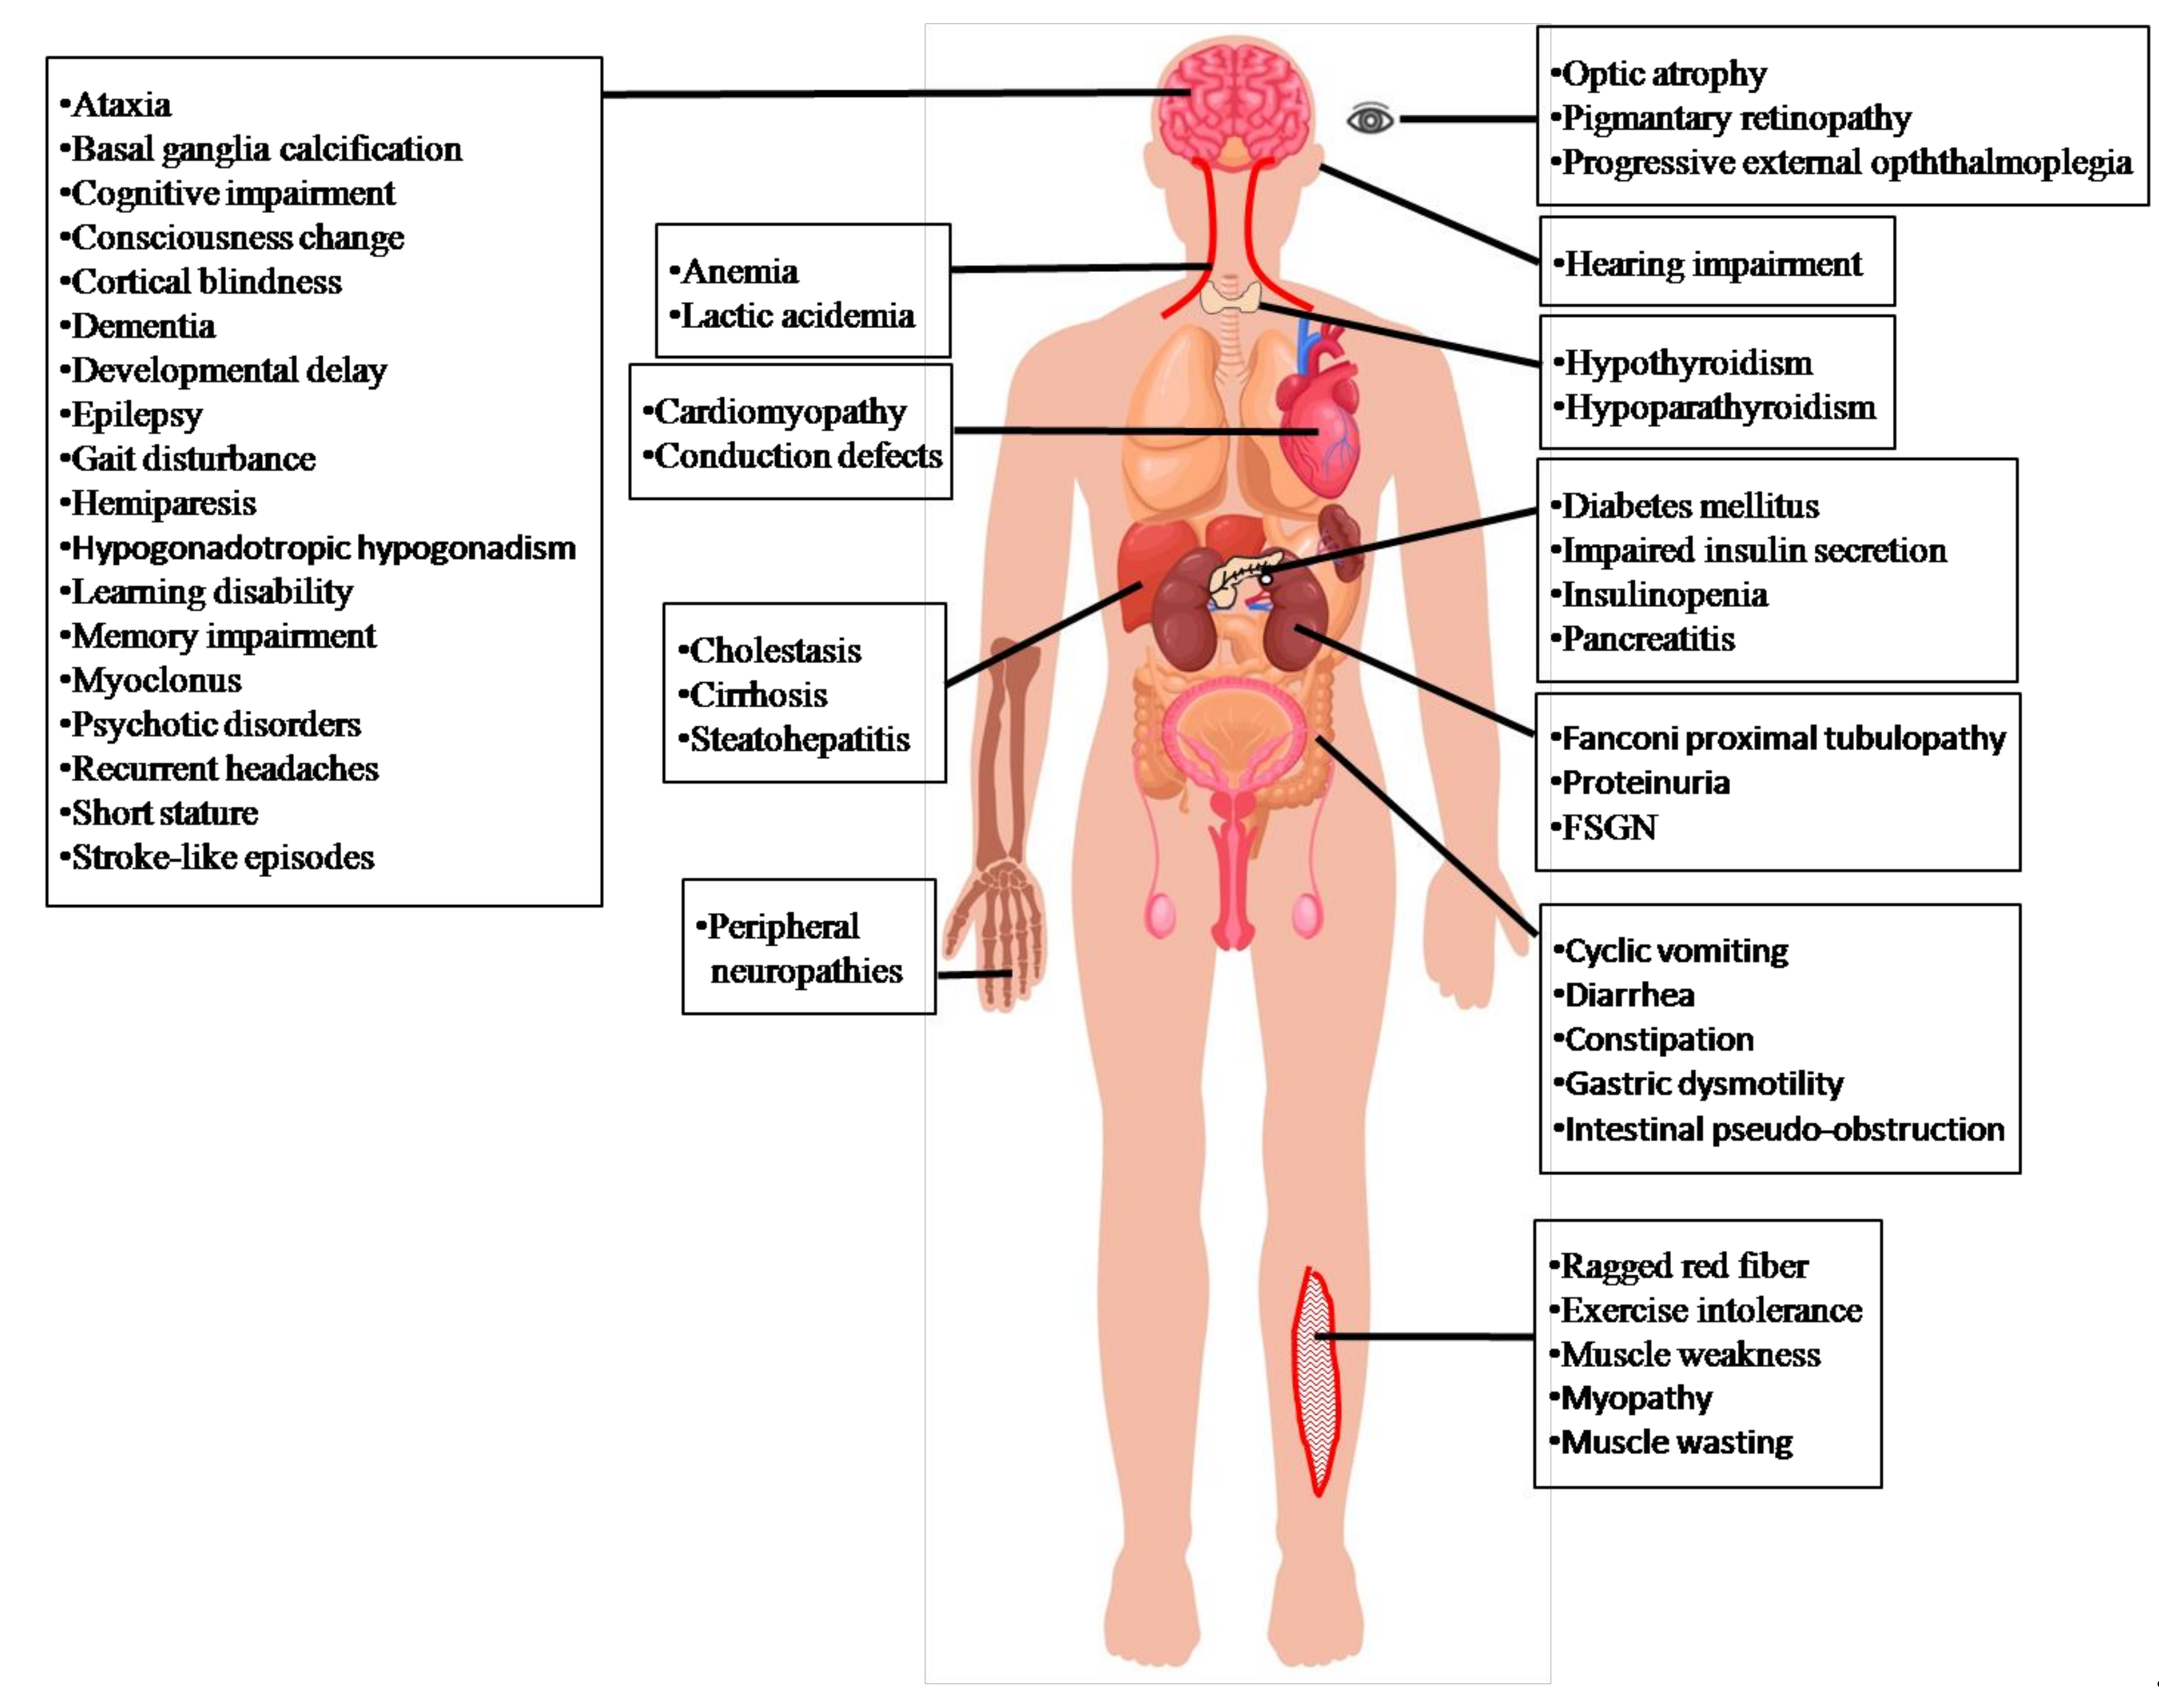

2. Clinical Manifestations of Mitochondrial Encephalomyopathy, Lactic Acidosis, and Stroke-Like Episodes (MELAS) Syndrome